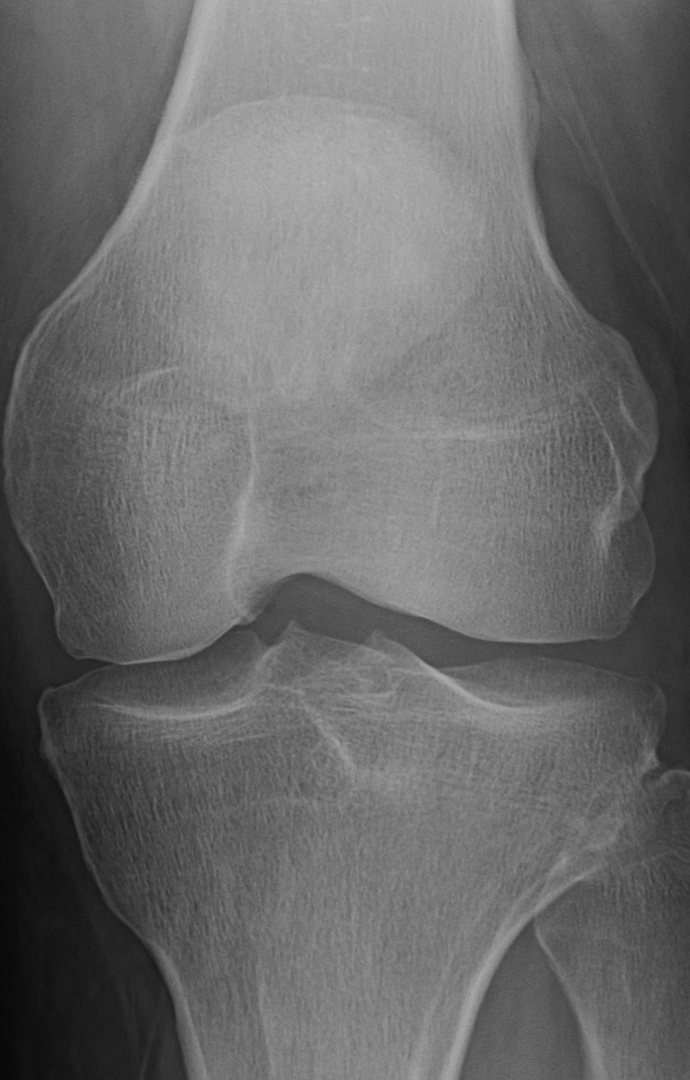

Your sunrise pateler views (bottom knee cap floating in space view) are worrying. You are developing bone avulsions (the part where it looks like it is separating) most likely due to impact injury coupled with straining tendons. You got to start wearing knee pads for what ever you are doing that is impacting them. If that continues in the same path, even walking will be a chore.